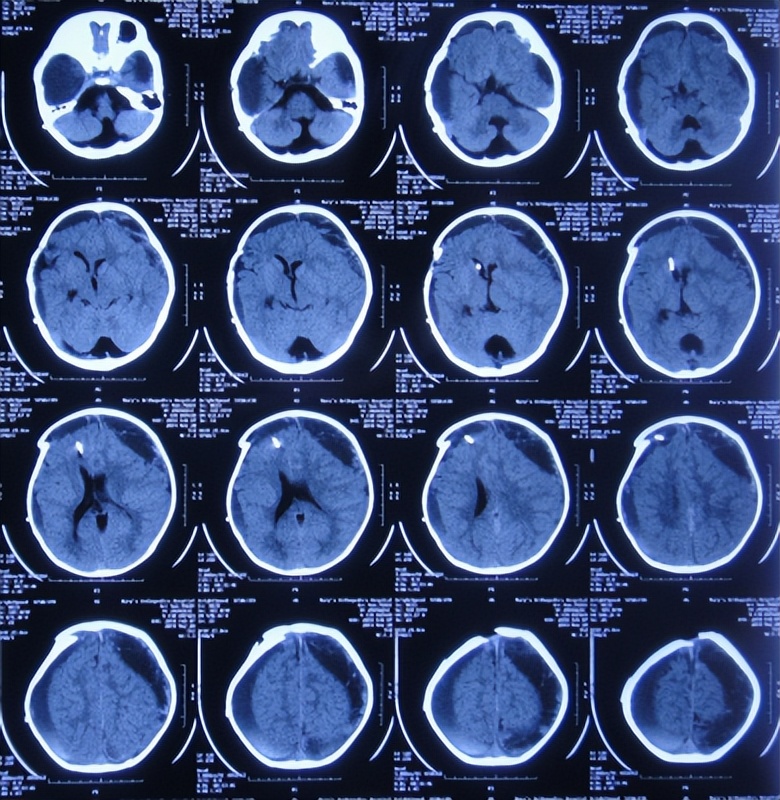

入院后5天即2018年9月18日,进行了双侧颞叶蛛网膜囊肿脑池沟通术。但术后次日,患儿出现恶心呕吐,复查头颅CT示双侧硬膜下积液( 图-3 )。

图-3: 2018年9月19日头颅CT